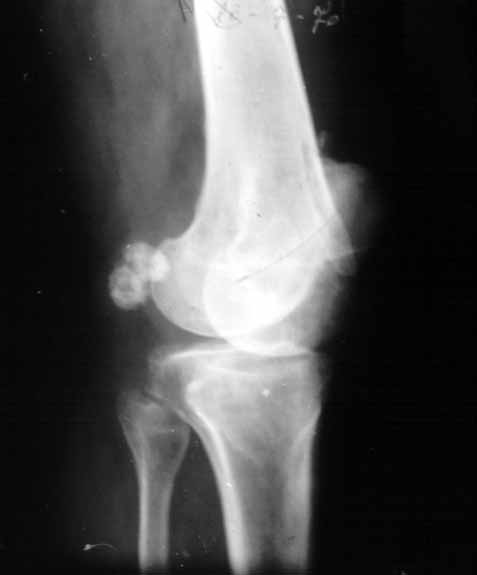

La condromatosis sinovial primaria ocasiona sintomatología monoarticular , con dolor ,inflamación y limitación funcional. Pueden afectarse las bursas y vainas tendinosas aunque la localización mas habitual es la intraarticular . La rodilla es la mas afectada, 50% de los casos, seguida de la cadera y tobillo. (28) La edad de presentación es variable y es mas frecuente en varones que en mujeres, en una proporción de 2:1. Para su diagnóstico sigue teniendo gran interés la radiología simple (29). Los signos radiográficos son muy característicos (figura 14) , si los cuerpos libres están calcificados (osteocondromatosis) , siendo difícil su interpretación si son radiotransparentes (condromatosis ). Los signos radiográficos directos consisten en la presencia de cuerpos extraños intraarticulares calcificados de tamaño variable, mas o menso numerosos pero siempre múltiples (figura 15a y b). Los signos indirectos son menso demostrativos , erosiones óseas por la hipertrofia sinovial, aumento de la interlínea articular por la interposición de cuerpos extraños o artrosis que debuta con perdidas de cartílago . La resonancia nuclear magnética permite el diagnóstico diferencial con las sinovitis y localiza la presencia de cuerpos extraños desarrollados eventualmente en las bolsas serosa contiguas. La artrografía opaca está indicada ante una sospecha clínica sin cuerpos calcificados.